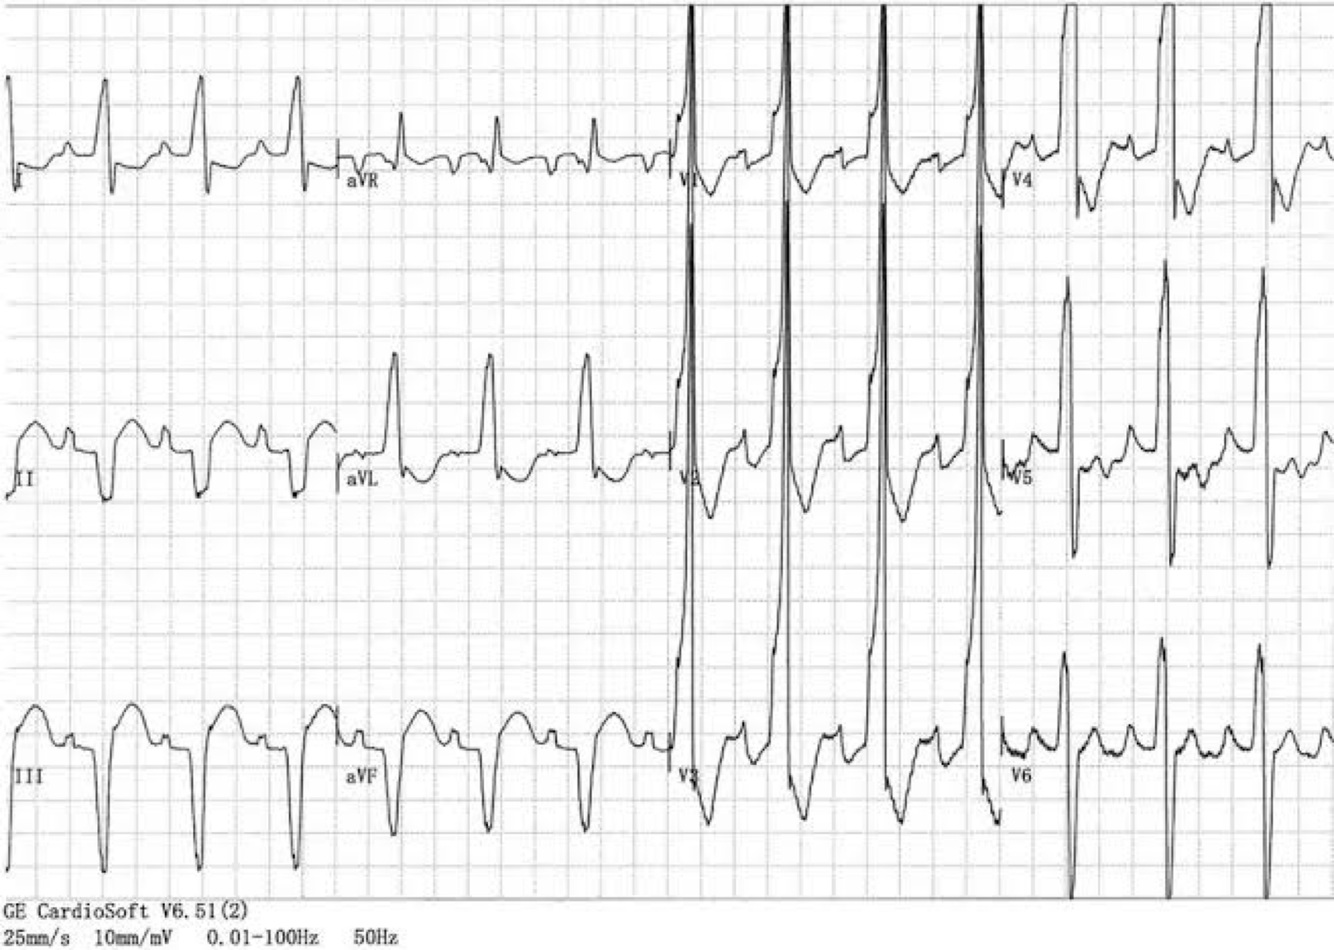

⛔️BLOQUEIO🎭MASCARADO  :

BDR em precordiais

➕

BRE em D1 sem onda S

⛔️BLOQUEIO MASCARADO 🎭:

▪️presença de morfologia característica de BRD no plano horizontal (V1-V6)

ASSOCIADO a morfologia de BRE c/desvio do eixo p/esquerda no plano frontal (DI ,aVL)

▪️Este tipo de BRD é causado pela associação simultânea com BDAS de alto grau frequentemente acompanhado por SVE grave🏋️‍♂️

E/OU Bloqueio Focal 🎯da parede anterolateral do VE devido a infarto do miocárdio ou fibrose.

▪️Na maioria dos casos típicos de BRD

c/BDAS, o eixo elétrico 🧭 no plano frontal encontra-se entre -80° e -120°, ENTRETANTO, ⚠️

quando o eixo permanece próximo a -60°,devido ao predomínio de forças ventriculares esquerdas,

o BRD c/ BDAS será acompanhado que onda “S” muito pequena OU AUSENTE em D1, simulando o padrão de BRE nesta derivação.

▪️O BRD com BDAS pode imitar o BRE tanto nas derivações dos membros (mascaramento padrão) com

🚫AUSÊNCIA de onda “S” em D1, quanto nas derivações precordiais (mascaramento precordial) com

🚫DESAPARECIMENTO da

onda “S” em V5 e V6.

▪️Em ambos os casos o BRD pode ser reconhecido pelo seu padrão típico em V1.

▪️Vale ressaltar que este padrão está associado a pior prognóstico e implica doenças subjacentes graves.

🧨Ex: risco de evoluir com BAVT em 1-2 anos é 20-30%